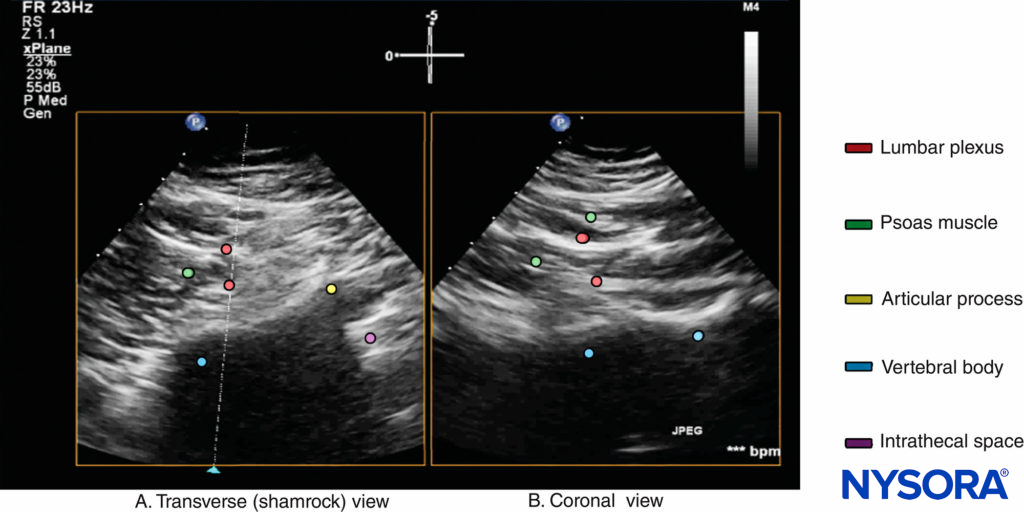

After it exits the intervertebral foramen, the lumbar nerve root does not enter the psoas muscle directly opposite the intervertebral foramen from which it emerges (see Figure 14), but takes a steep caudal course (see Figure 14), entering the psoas muscle at the vertebral level below to join the lumbar plexus. The lumbar plexus is seen as a separate hyperechoic structure within a hypoechoic space, the psoas compartment, in the posterior aspect of the psoas muscle (see Figure 14). In a transverse sonogram produced by the shamrock method (see Figure 15), the psoas, erector spinae, and quadratus lumborum muscles are also clearly visualized (see Figures 16, 17, 18 and 19). The anatomical arrangement of the three muscles around the transverse process—that is, the psoas muscle lying anteriorly, the erector spinae muscle lying posteriorly, and the quadratus lumborum muscle lying at the apex (see Figure 16)—produces a sonographic pattern that has been likened to the shape of a “shamrock,” with the muscles representing its three leaves. The lumbar nerve root may also be visualized close to the angle between the vertebral body and the transverse process (see Figure 16) and the lumbar plexus within the posterior aspect of the psoas muscle, typically about 2 cm anterior to the transverse process (see Figures 17 and 18). From this position, if the transducer is gently tilted caudally, the acoustic shadow of the L4 transverse process disappears, and the US beam is now insonated through the intertransverse space and at the level of the articular process of the L4 vertebra, similar to that seen with a PMTOS-AP (see Figure 17). As a result, apart from the psoas, erector spinae, and quadratus lumborum muscles, the intervertebral foramen and lumbar plexus may also be visualized (see Figure 17).

FIGURE 18. Biplanar US image of the lumbar paravertebral region obtained with the shamrock method, with the US beam insonated through the lumbar intertransverse space and at the level of the articular process. Note that the transverse axis (A) is the primary data acquisition plane and that the corresponding orthogonal image along the secondary data acquisition plane (dotted line with blue arrowhead in [a]) is a coronal view (B) showing the lumbar plexus nerves within the psoas muscle.